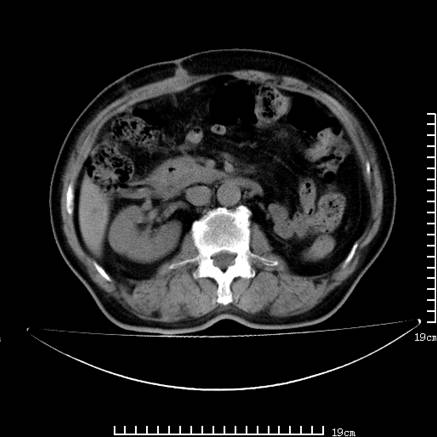

以下是引用zsl6918在2008-7-19 21:53:00的发言:[br]胆总管结石并胆系感染,胆囊切除术后改变。

以下是引用sch2008在2008-7-19 22:03:00的发言:[br]肝内胆管及胆总管积气,并胆总管结石,考虑;胆囊切除术后,胆系感染

以下是引用xinliheng001在2008-7-19 21:59:00的发言:[br]胰头段胆管结石肝内外胆管扩张积气。

以下是引用liaoqiang在2008-7-19 22:26:00的发言:[br]胆总管结石伴胆系感染。